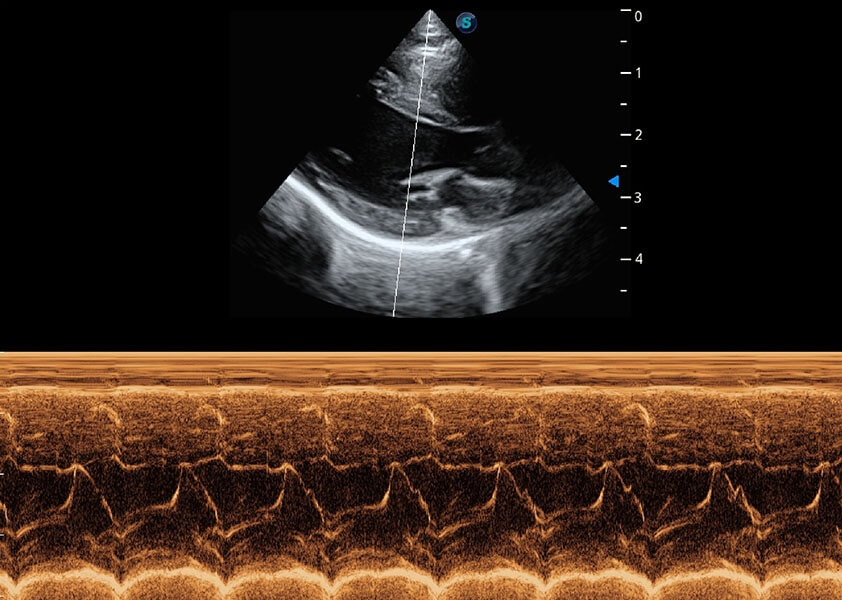

• AMM 解剖M型

通過(guò)360度任意調(diào)節(jié)3條M型取樣線(xiàn),在同一心動(dòng)周期上觀察心臟不同位置的運(yùn)動(dòng)曲線(xiàn),得到準(zhǔn)確的心功能測(cè)量數(shù)據(jù),有效評(píng)估心肌運(yùn)動(dòng)及左心室功能。

(貓)二尖瓣M型